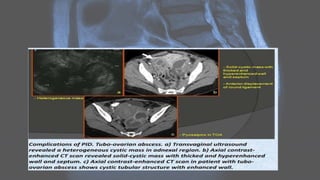

PELVIC INFLAMMATORY DISEASE

• Pelvic inflammatory disease (PID) is a broad term that encompasses a

spectrum of infection and inflammation of the upper female genital

tract, resulting in a range of abnormalities.

• PID is defined as an acute clinical syndrome associated with ascending

spread of micro-organisms, unrelated to pregnancy or surgery. The

infection generally ascends from the vagina or cervix (cervicitis) to the

endometrium (endometritis), then to the fallopian tubes (salpingitis,

hydrosalpinx, pyosalpinx), and then to and/or contiguous structures

(oophoritis, tubo-ovarian abscess, peritonitis).

Radiographic features

Ultrasound

• Ultrasound is usually the first imaging requested in a case of lower abdominal pain.

• Early findings in PID include :

• indistinct uterine margins

• echogenic pelvic fat

• fallopian tube thickening

COG WHEEL APPEARANCE STRING ON A BEADS APPEARANCE

CT IMAGING

• tubular adnexal "mass"

• fallopian tube thickening of >5 mm with enhancing wall: has high specificity of 95%

• indistinct uterine border

• thickening of the uterosacral ligaments

• complex free fluid in the pouch of Douglas (cul-de-sac)

• pelvic fat stranding or haziness

• reactive lymphadenopathy

MRI

• May show an ill-defined adnexal mass containing fluid with various

signal intensities:

• T1: if there is proteinaceous debris in a dilated tube, then it may have

increased T1 signal

• T1+C (Gd): wall and surrounding tissues may enhance